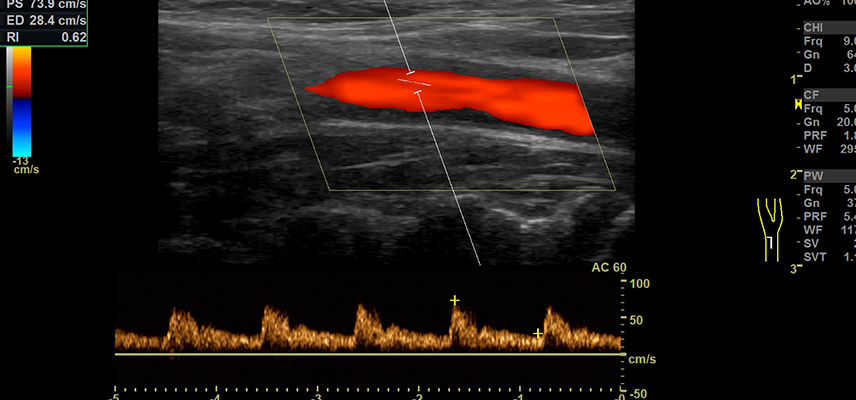

Bei einer medizinischen Ultraschall-Untersuchung werden zunächst durch einen Schallkopf Ultraschallwellen impulsartig in den Körper gesendet. Beim Weg durch den Körper werden die Schallwellen im Gewebe unterschiedlich stark absorbiert und reflektiert. Es wird von den Muskeln, Knochen oder Organen ein Echo erzeugt, welches wiederum durch den Schallkopf aufgefangen wird. Einerseits kann durch die Zeit, welche das Echo braucht, die Entfernung einer Gewebeschicht oder eines Organs zur Oberfläche ermittelt werden. Andererseits bietet die zurückgeworfene Stärke des Echos Einblicke in die Art des untersuchten Gewebes; beispielsweise führen Knochen aufgrund ihrer Härte zu deutlich stärkeren Reflexionen als weichere Organe. Die verschiedenen und unterschiedlich starken Echos, die sich auf dem Weg durch den Körper bilden, lassen ein Bild entstehen, welches in Echtzeit am Monitor dargestellt werden kann. Mit Hilfe des sogenannten Doppler-Verfahrens können Flussgeschwindigkeit und Flussrichtung von arteriellem und venösem Blut beurteilt werden.

Die Sonographie hat als schnell durchzuführende und nicht belastende Untersuchung ein breites Anwendungsspektrum in der Diagnostik gefunden. Dieses Verfahren eignet sich sehr gut zur Darstellung der Organe des Bauchraumes (Leber, Gallenblase, Nieren oder Harnblase), des Halses, der Schilddrüse sowie der Brustdrüse (Mamma). Ferner ist auch der Blutfluss unter Verwendung des sogenannten Dopplerprinzips (Doppler-Sonografie) darstellbar und kann beurteilt werden. Mittels Sonographie ist es möglich, Hinweise auf Organerkrankungen wie Krebs, Entzündungen oder andere Gewebeveränderungen zu erhalten.